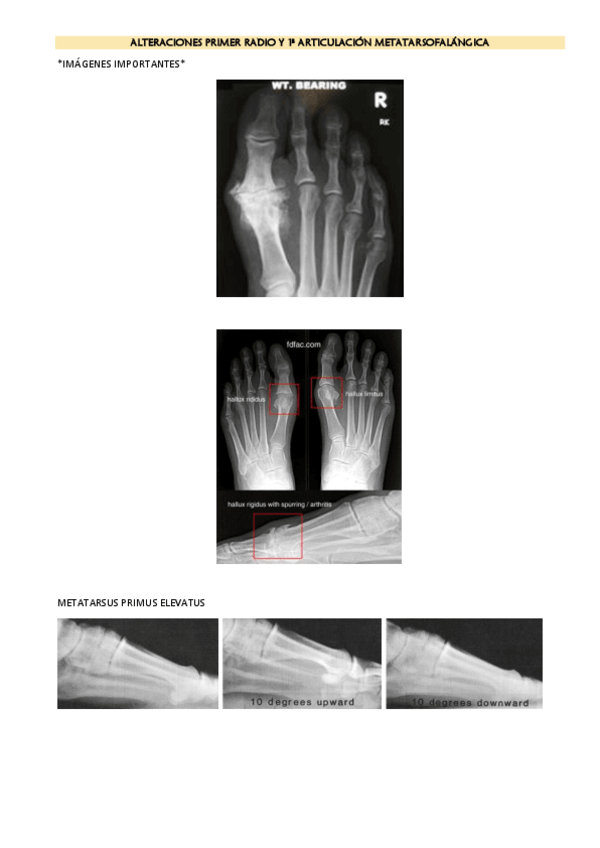

ALTERACIONES-PRIMER-RADIO-Y-1a-ARTICULACION-METATARSOFALANGICA-IMAGENES.pdf